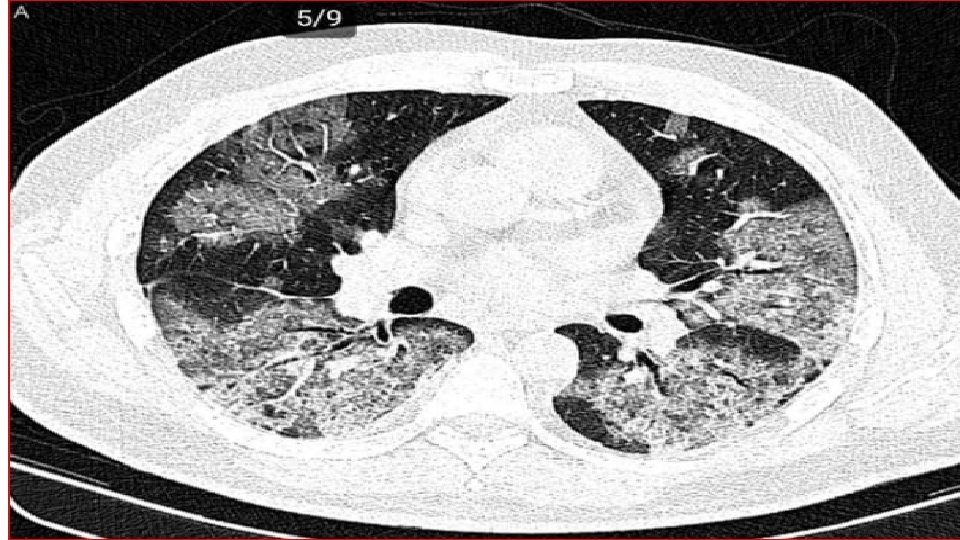

Chest X-ray An X-ray : look for signs of inflammation in chest. If inflammation is present, the X-ray can also inform about its location and extent.

In COVID-19 pneumonia Leukopenia in ~70% of hospitalized patients. LDH may be modestly elevated. LFTs elevated more commonly than in typical Community-Acquired Pneumonia cases. Chest CT may show ground-glass opacities that may evolve into consolidation or ARDS. Findings appear to peak at 10 d of illness, resolution begins after day 14. CT may show lung findings (such as ground-glass opacities) before the development of symptoms. Among hospitalized patients, about one-third need to be in the ICU/intubated with an ARDS picture. Elevations in IL-6 (> 40– 100), CRP (> 10 x normal), ferritin (> 1000) suggested correlating with a cytokine release syndrome-like picture and impending ARDS.